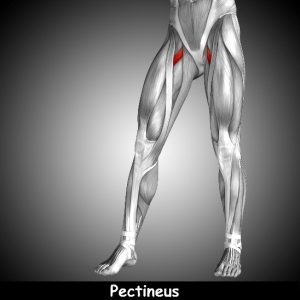

The pectineus muscle is in your adductor muscle group. The adductors are responsible for hip flexion and adduction.

As you look at the graphic on the left, the muscles on the left side (right leg) are the larger adductor muscles.

As you look at the graphic on the left, the muscles on the left side (right leg) are the larger adductor muscles.

The pectineus is shown on the right side (left leg) so that it is more visible, helping you see the location of the muscle. In reality, all the muscles are on both sides.